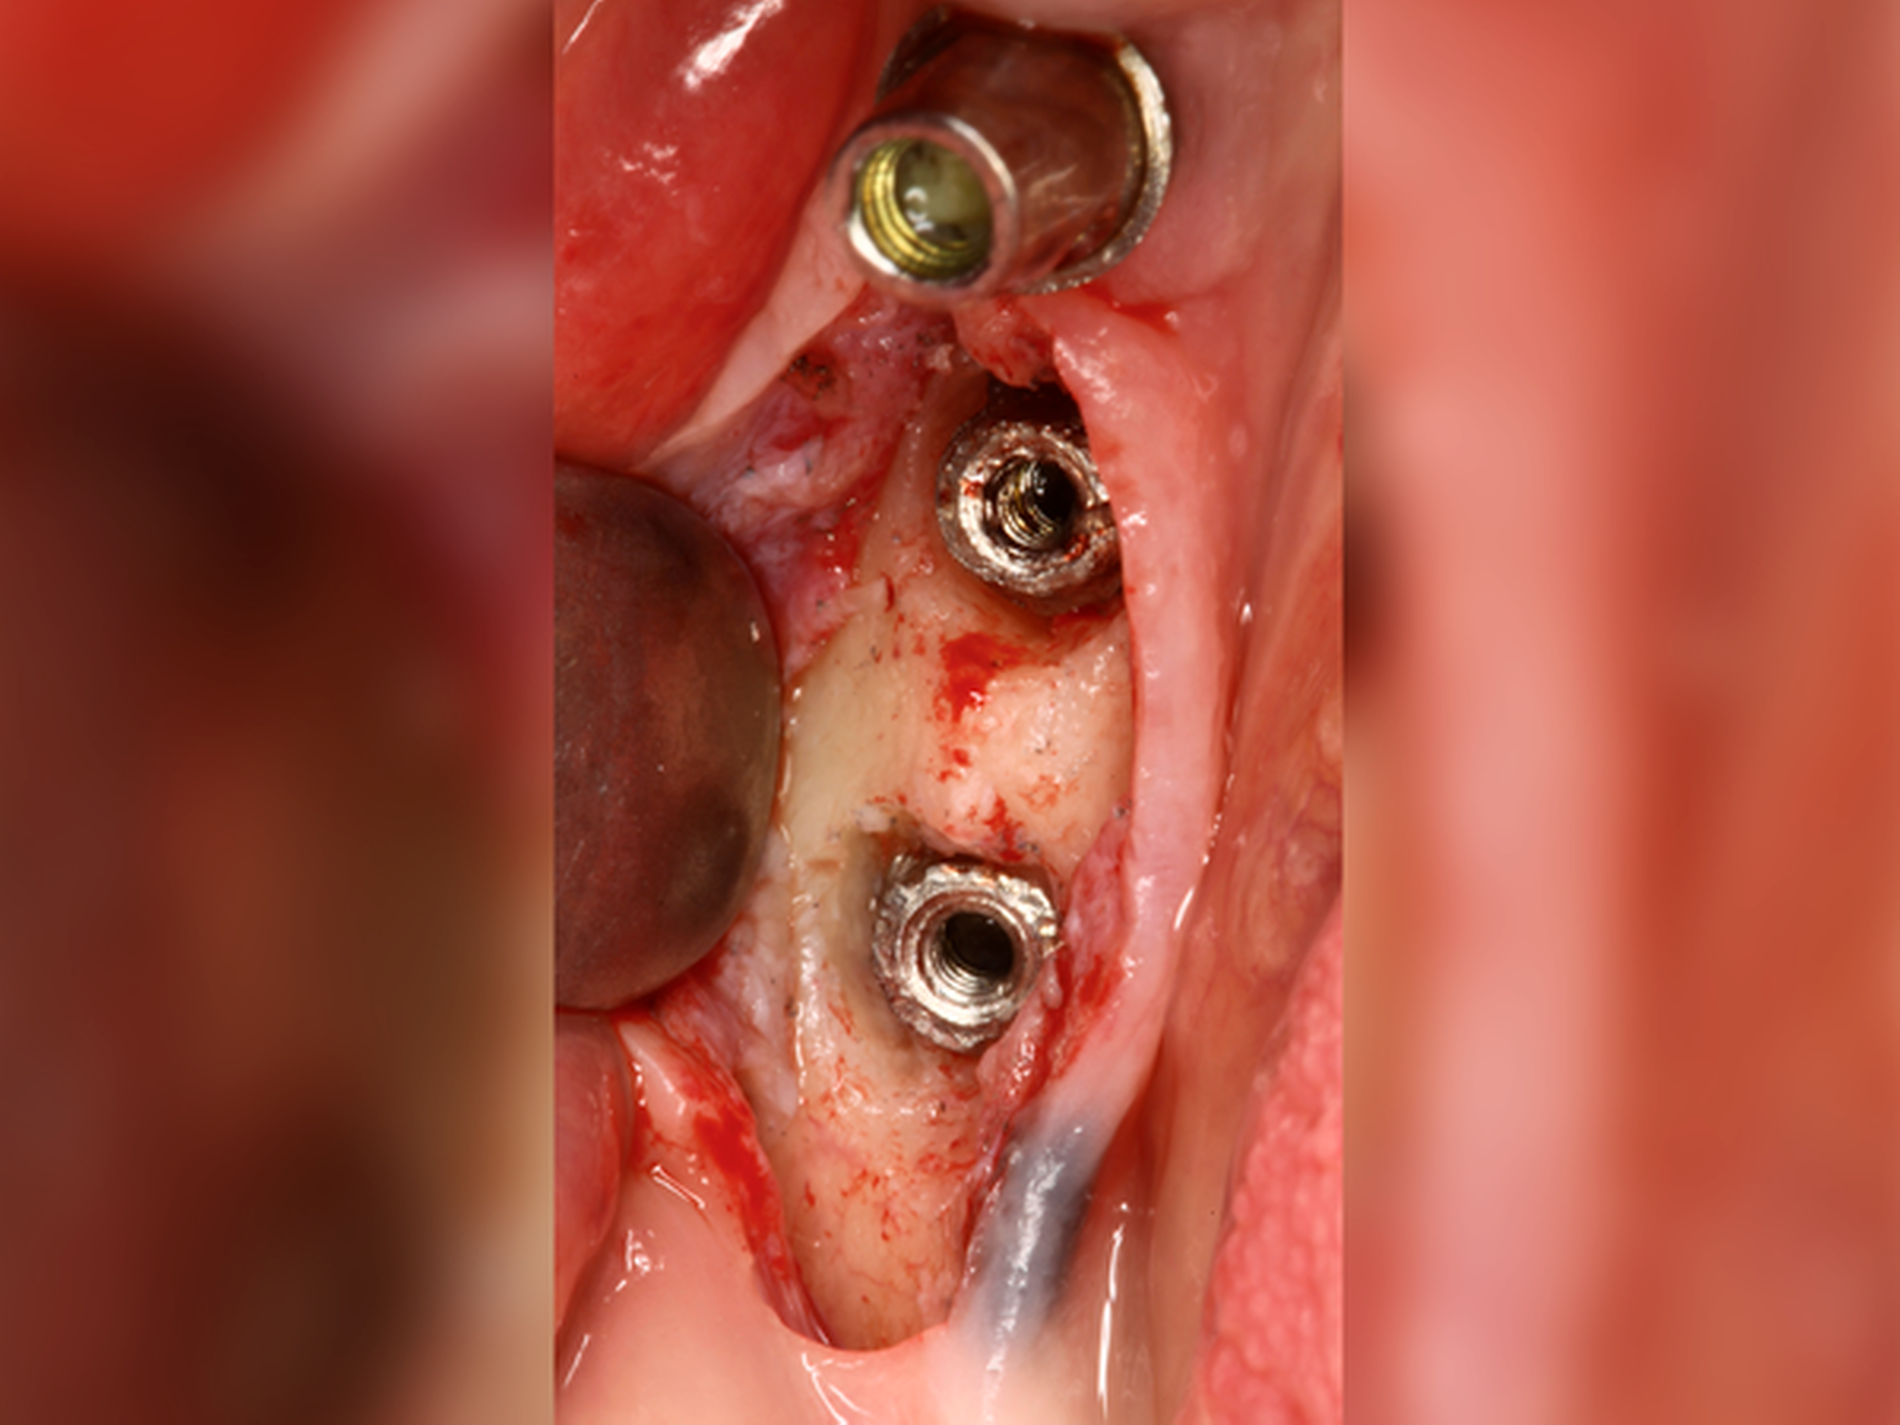

Wenn wir über technische Komplikationen in der Implantologie nachdenken, dann fallen uns sicher zuerst Dinge wie Keramikabplatzungen der Suprakonstruktion, Schraubenlockerungen, Gerüstfrakturen oder Retentionsverluste ein. Schraubenbrüche und Abutmentbrüche gehören Gott sei Dank nicht zu unserem Alltag, genauso wenig wie die schlimmste technische Komplikation: der Bruch des osseointegrierten Implantats (Abbildungen 1 und 2). Sicher kennen die meisten Kolleginnen und Kollegen aus ihren Praxen frakturierte Implantate als eher seltene Ereignisse – die jedoch meist einen sehr großen Behandlungsaufwand nach sich ziehen. Aber wie viele Implantate brechen wirklich beziehungsweise wie hoch ist das Risiko für eine Implantatfraktur?